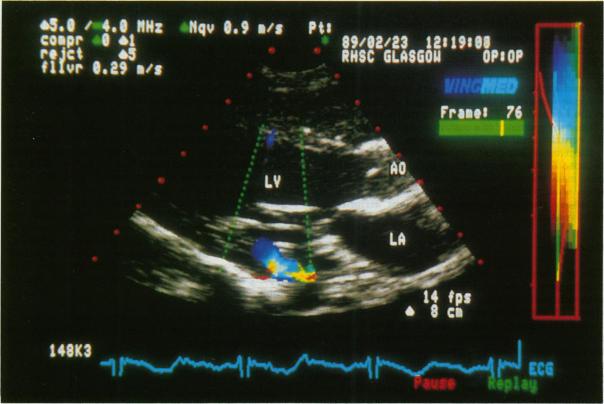

左心室与冠状窦之间的先天性瘘管:彩色多普勒血流图的阐明

Congenital fistula between the left ventricle and coronary sinus: elucidation by colour Doppler flow mapping.

A fistula between the left ventricle and the coronary sinus was diagnosed by Doppler echocardiography and confirmed by cardiac catheterisation in a symptom free child who presented with clinical signs of mitral regurgitation. A similar abnormality has been reported after repeated mitral valve replacement and after myocardial infarction but a congenital fistula of this type has not been described before.

一名二尖瓣反流临床体征明显但无症状的儿童,通过多普勒超声心动图诊断出左心室与冠状窦之间存在瘘管,并经心导管检查得以证实。此前已有报道称,在反复进行二尖瓣置换术后以及心肌梗死后会出现类似异常,但此前尚未描述过这种类型的先天性瘘管。